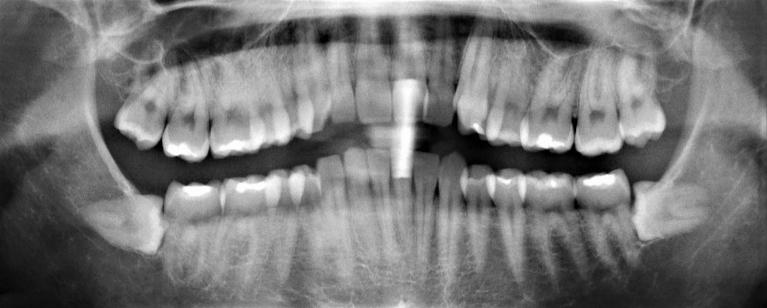

It’s important to understand that removing a tooth is never a dentist’s first choice. Preserving tooth structure, even if it’s compromised, is always preferable to removing the tooth.

If we’ve recommended tooth extraction, it’s because it’s the only option that will protect your oral health and your remaining teeth. Sometimes, removing a tooth will help us deliver the best results in conjunction with other procedures: